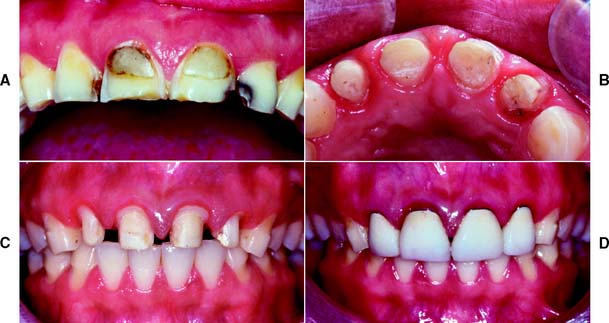

Margins should not be placed so far apically that they encroach on the attachment; extension to within 1.5 mm of the alveolar crest leads to bone resorption.110 The margin should follow the contour of the free gingiva, being further apical in the middle of the tooth and further incisal interproximally. A common error (Fig. 7-51) is to prepare the tooth so the margin lies almost in one plane, with exposure of the collar labially and irreversible loss of bone and papilla proximally.

Fig. 7-51 Poor preparation design. A, These badly damaged incisors were treatment planned for metal-ceramic crowns. B and C, The apical margin of the preparation does not follow the free gingival contours. D, The restoration displays a metal collar labially, and the deep proximal margins have led to periodontal disease.